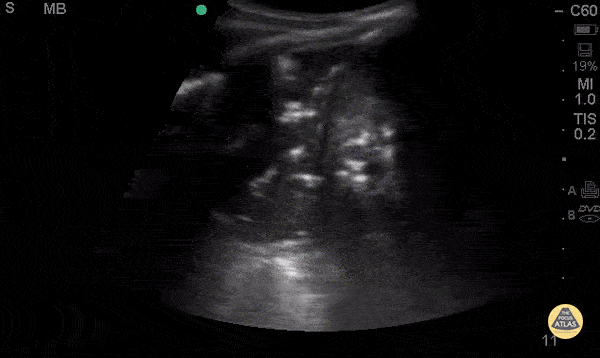

A 54-year-old with fever, pleuritic discomfort, and shortness of breath has focal crackles, but the chest X-ray is still pending. Lung ultrasound is shown. What are the findings? What is diagnosis?

Findings: What is consolidation with dynamic air bronchograms?

Diagnosis: What is pneumonia?